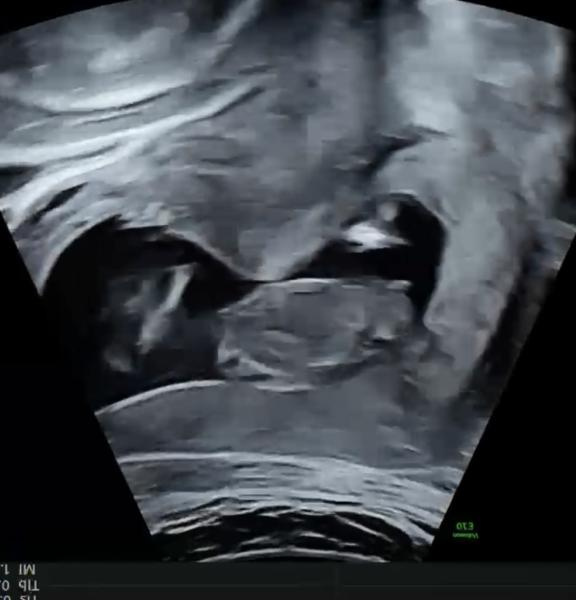

Hej ni får jätte gärna spekulera i vad det är för kön på min bebis v12+5